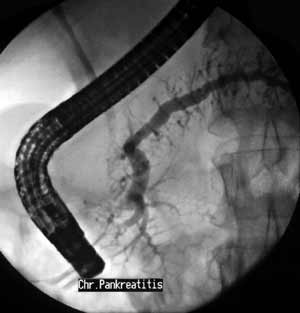

Рентгеноскопия + эндоскопия = ЭРХПГ.

Рис. 3. Признаки хронического панкреатита: расширение панкреатического протока и ветвей 2-3-го порядка, неровность контуров протока и ветвей.